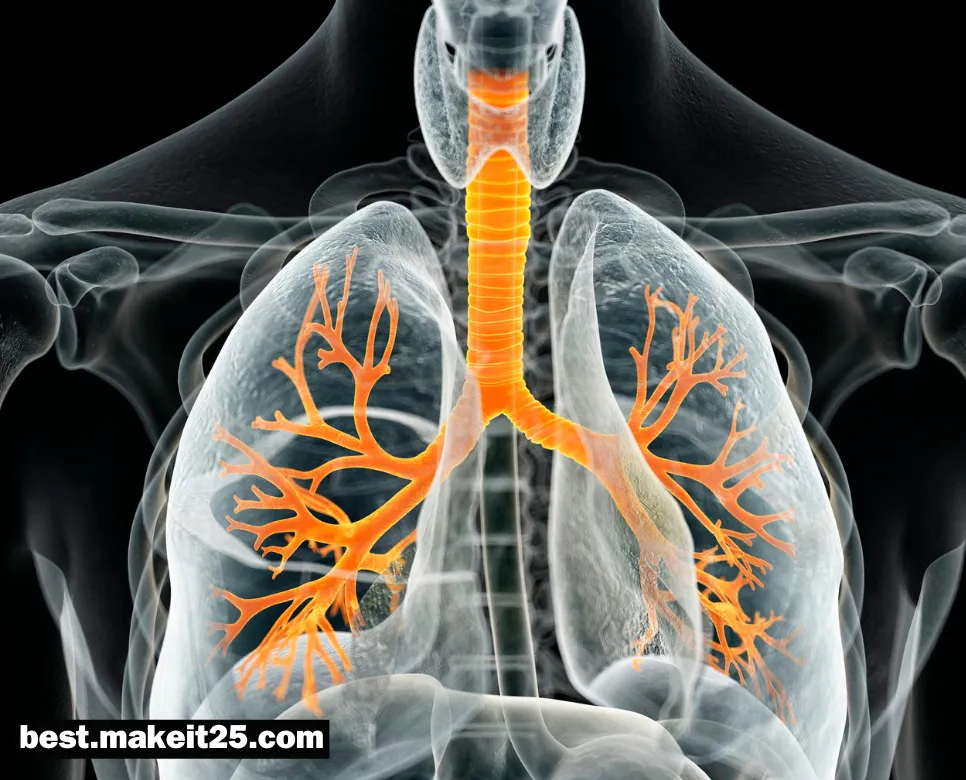

PCD는 의학 용어로 Primary Ciliary Dyskinesia의 약자이며, 한글로는 ‘원발성 섬모 운동 이상증’을 의미합니다. 이는 섬모의 구조 또는 기능에 이상이 있어 섬모 운동이 제대로 이루어지지 않는 유전 질환입니다. 섬모는 호흡기, 생식기 등 여러 기관에 존재하며, 점액과 이물질을 제거하고 체액의 이동을 돕는 역할을 합니다. PCD 환자는 섬모 기능 장애로 인해 반복적인 호흡기 감염, 만성 기침, 불임 등 다양한 증상을 경험하게 됩니다.

- 호흡기 증상: 만성 기침, 만성 비염, 만성 중이염, 반복적인 폐렴 등이 나타날 수 있습니다.

요약하면, PCD는 섬모 기능 이상으로 인해 발생하는 유전 질환으로, 반복적인 호흡기 감염, 불임, 내장 위치 이상 등의 증상을 유발합니다. 특징적인 임상 양상, 섬모 기능 검사, 유전자 검사 등을 통해 진단하며, 예방적 항생제 투여, 호흡기 물리치료, 불임 치료 등의 방법으로 관리합니다. PCD는 드문 질환이지만, 조기 진단과 적절한 치료를 통해 환자의 삶의 질을 개선할 수 있습니다.